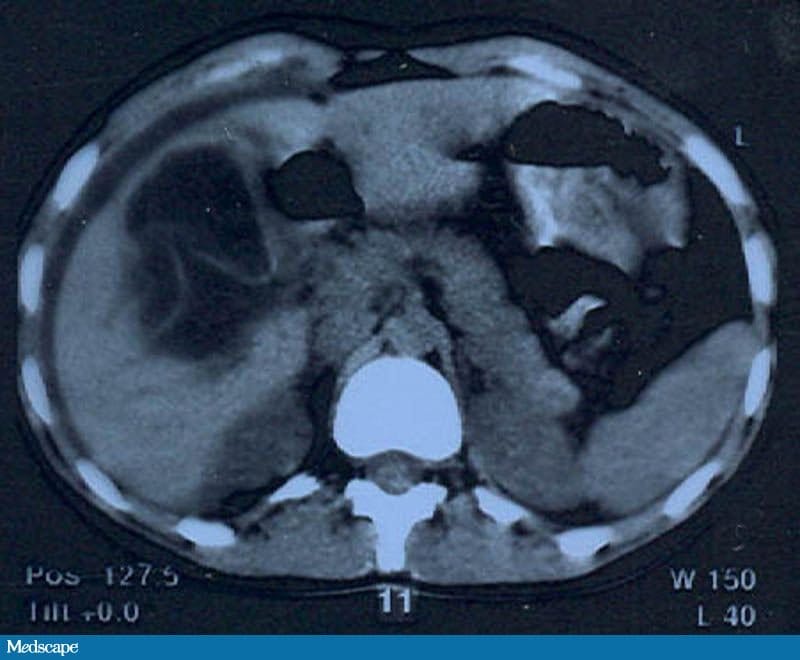

Uma radiografia do abdome em posição ortostática mostra um padrão de gases intestinais inespecífico, sem pneumoperitônio. É feita uma ultrassonografia por suspeita de possível doença da vesícula biliar; o exame revela uma grande zona hipoecoica hepática com margens irregulares e uma pequena quantidade de líquido livre circundando o fígado. Na sequência, é feita a tomografia computadorizada (TC) do abdome (Figuras 1 e 2).

Figura 1.